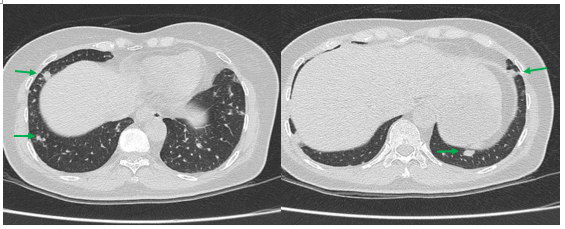

Hình 2: Hình ảnh cắt lớp vi tính ngực có tiêm: Rải rác nốt đặc 2 bên thùy phổi kích thước 3-10mm (các mũi tên màu xanh lá)

Hình 3: Hình ảnh cắt lớp vi tính ngực có tiêm: Trung thất các nhóm 1R; 2R; 4R; 5; 8; 10RL có vài hạch lớn nhất kích thước 26x15mm; bờ không đều; ngấm thuốc không đồng nhất sau tiêm (mũi tên màu cam)

- Cắt lớp vi tính lồng ngực: đám xẹp đông đặc đỉnh phổi phải kích thước 11mm; nhu mô phổi rải rác nốt đặc 5-10mm. Trung thất cân đối có vài hạch 10mm

Hình 6: Hình ảnh cắt lớp vi tính ngực có tiêm: đám xẹp đông đặc đỉnh phổi phải kích thước 11mm (mũi tên xanh nước biển)

Hình 7: Hình ảnh cắt lớp vi tính ngực có tiêm: Trung thất cân đối có vài hạch 10mm (mũi tên vàng). Hạch trung thất giảm kích thước rất nhiều chỉ sau 03 chu kỳ.